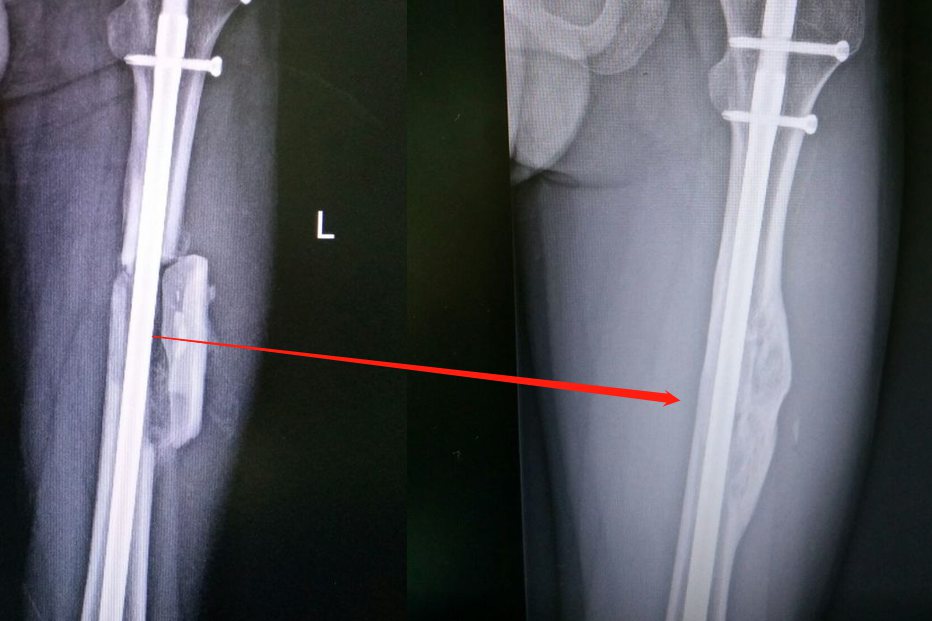

骨痂开始形成的时间一般是骨折术后的4~6周,与骨折部位血供相关。骨折术后修复首先是骨样连接,然后才在骨外膜、骨内膜部位形成骨痂。骨折术后一百天可在X线下看到骨折处出现梭形骨痂阴影,隐约可见骨折线。此时的骨痂还是原始骨痂,骨小梁相对较少且排列较为紊乱和疏松。骨痂形成后还需要经过钙化、改造塑形阶段才可以使骨折部位恢复如初。